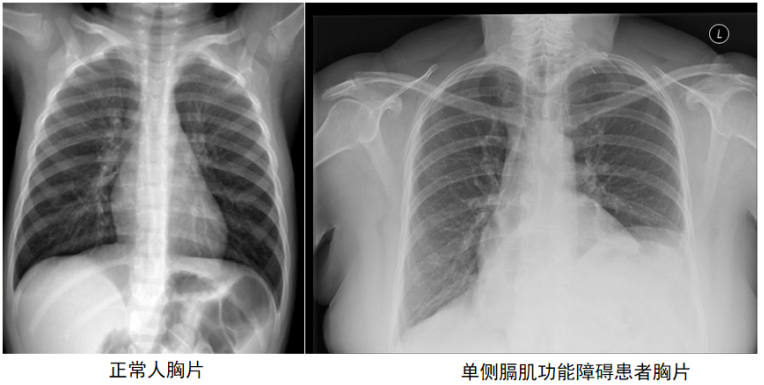

一般来说,正常人的胸片,右侧膈肌会略高于左侧膈肌(高出1~2个肋间不等),但如果左侧膈肌明显高于右侧膈肌,就要考虑单侧膈肌功能障碍的可能(图1),需要进一步检查。

图1  正常人与单侧膈肌功能障碍患者胸片比较